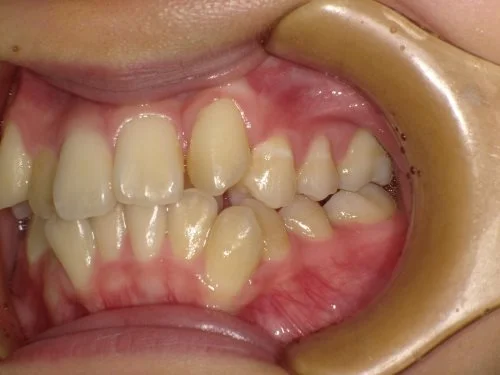

<症例7>歯がガタガタで噛み合わせが悪くお悩み

抜歯無し・マウスピースのみで矯正した症例です。

もともと歯列弓が非常に狭く、V字に近い形をしていたので噛み合わせも非常に不安定でした。

また、下顎前歯部がかなり上の方に生えていたため、下の前歯が上の前歯を突き上げてしまい出っ歯の状態になっていました。

現在では見た目はもちろん、臼歯の噛み合わせも改善しております。

奥歯の患者様も大喜びでした。

患者様と症状

主訴:歯のガタガタ、噛み合わせが悪い

性別・年齢:20代女性

問題点:叢生(重度)、V字歯列弓、ディープバイト

診断:前歯部の叢生を伴うアングルⅠ級、骨格性Ⅰ級の不正咬合

主なリスク:臼歯の移動に伴い一時的に咬合しにくくなる、歯肉退縮

症状:叢生(そうせい) 過蓋咬合(かがいこうごう)

治療内容

治療期間:1年10ヶ月

治療費用:990,000円(税込)

プラン:Full2プラン

抜歯:無し

再診治療費:無し

追加治療費:無し

保定装置費:無し

治療前後の写真